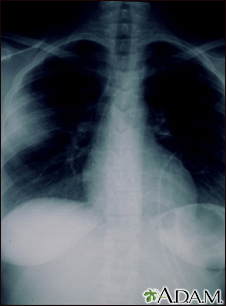

Aspergillosis - chest x-ray